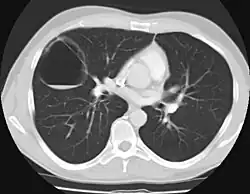

Diagnosis

CPAM on chest radiograph in a newborn. Large cystic changes in the left lung, leading to a mediastinal shift to the right due to their mass effect.

CPAMs are often identified during routine prenatal ultrasonography. Identifying characteristics on the sonogram include: an echogenic (bright) mass appearing in the chest of the fetus, displacement of the heart from its normal position, a flat or everted (pushed downward) diaphragm, or the absence of visible lung tissue.

CPAMs are classified into three different types based largely on their gross appearance. Type I has a large (>2 cm) multiloculated cysts. Type II has smaller uniform cysts. Type III is not grossly cystic, referred to as the "adenomatoid" type. Microscopically, the lesions are not true cysts, but communicate with the surrounding parenchyma. Some lesions have an abnormal connection to a blood vessel from an aorta and are referred to as "hybrid lesions."